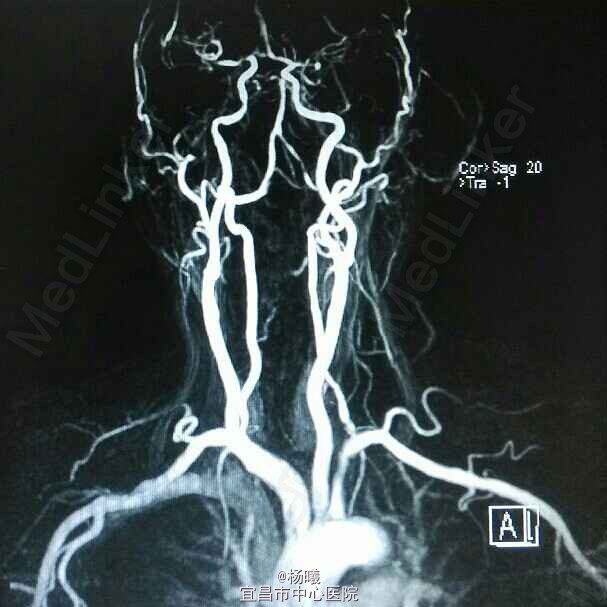

查体:BP 136/84mmHg,抬腿右下肢较左侧差,余无明显异常。 辅检:6-8 D-D 1.87,FIB 7.15,ALT 38,AST 46,GGT 37,LDL-C 4.38,铁蛋白 320,CRP 96.7,ESR 70,尿酮体1+ 6-15 PLT 469,ALT 53,GGT 50,ESR 38,D-D 0.59 血糖监测:早餐后高 彩超多普勒:升主动脉较宽,左室舒张功能减低;双侧颈动脉粥样硬化斑形成。 经颅多普勒:双侧颈内动脉、颈外动脉、左侧颈总动脉血流速度减慢;左侧锁骨下动脉、右侧大脑中动脉、大脑前动脉、左侧颈内动脉虹吸部管腔呈收缩状态;左侧颈内动脉虹吸部管腔重度狭窄;各检查动脉管腔应硬化。 头部MR、脑动脉造影MRA:脑干右侧11*12mm梗塞灶;腔隙性脑梗塞;脑萎缩;双侧额部顶部硬膜下积液;左侧椎动脉起始段及椎动脉-基底动脉汇合段管腔中度狭窄,双侧颈总、颈内外动脉、双侧大脑前中后动脉多发中-重度狭窄,动脉粥样硬化表现。

诊断:脑梗塞;高血压病3级 极高危;糖尿病 2型;动脉粥样硬化;高脂血症;慢性胃炎 治疗:依达拉奉、马来酸桂哌齐特、丹森川穹嗪注射,小牛血清去蛋白注射液;硝苯地平缓释片;阿司匹林肠溶片;阿托伐他丁钙片;阿卡波糖片。